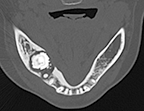

図❸ 初診時、軸位断CT

CT所見:軸位断では6部に不整形の塊状石灰化物を認め、周囲には帯状の透過像がみられ、その中に粒状の小石灰化像が散在していた。周囲の骨には硬化性変化がみられる(図❸)。